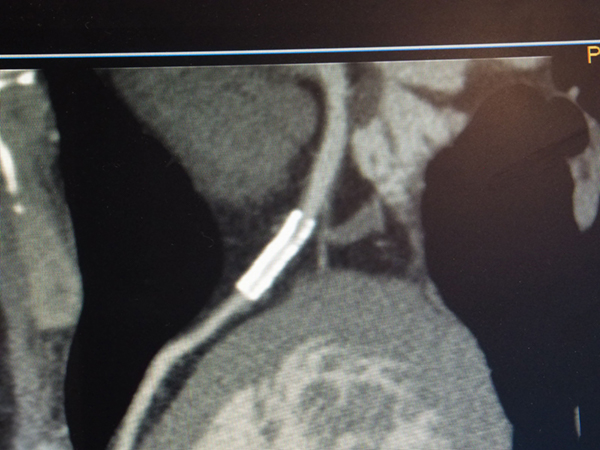

また,CT装置によってはDual Energy撮影の撮影範囲が限定されることがあるが,IQonシリーズは通常通り撮影した画像からDual Energy解析を行うため,撮影範囲に特別な制限はない。会場では,腕の外傷による救急症例で,受傷部だけでなく全身状態を評価するために上肢と体幹部を一緒に撮影し,後からMonoEで造影効果を向上させる処理を施した症例が紹介された。約45cmの広い範囲も問題なく撮影できており,緊急時にも短時間で高度な検査画像を提供できることが示された。

IQonシリーズでは広範囲(約45cm)のDual Energy解析も可能